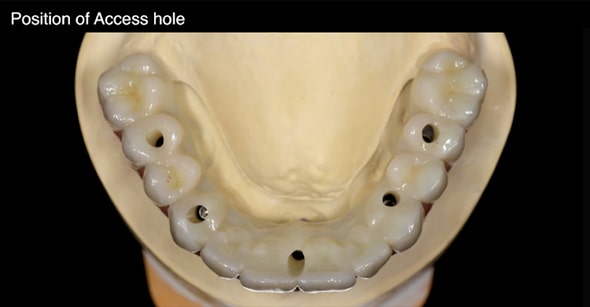

アクセスホールの位置

インプラント体と上部構造を連結するための穴を「アクセスホール」と呼びます。オールオンフォーでは、一般的に4つのアクセスホールを作成しますが、この位置関係が極めて重要になります。

インプラントの埋入位置について、事前に十分なシミュレーションを行っていない場合、その場凌ぎ的に不適切な箇所にアクセスホールを作ることになります。術前の診査・診断・プランニング、咬合力の強さや補綴物のスペースを考慮した治療計画を作成し、ガイデッドサージェリーによってインプラント埋入を行えば、このようなミスは決して発生しません。